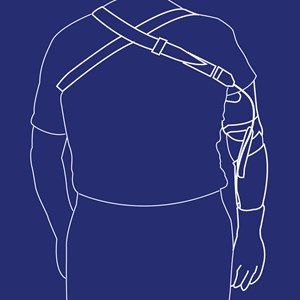

Helarmsortose (SEWHO)

Type: pdf

Størrelse: 861 KB